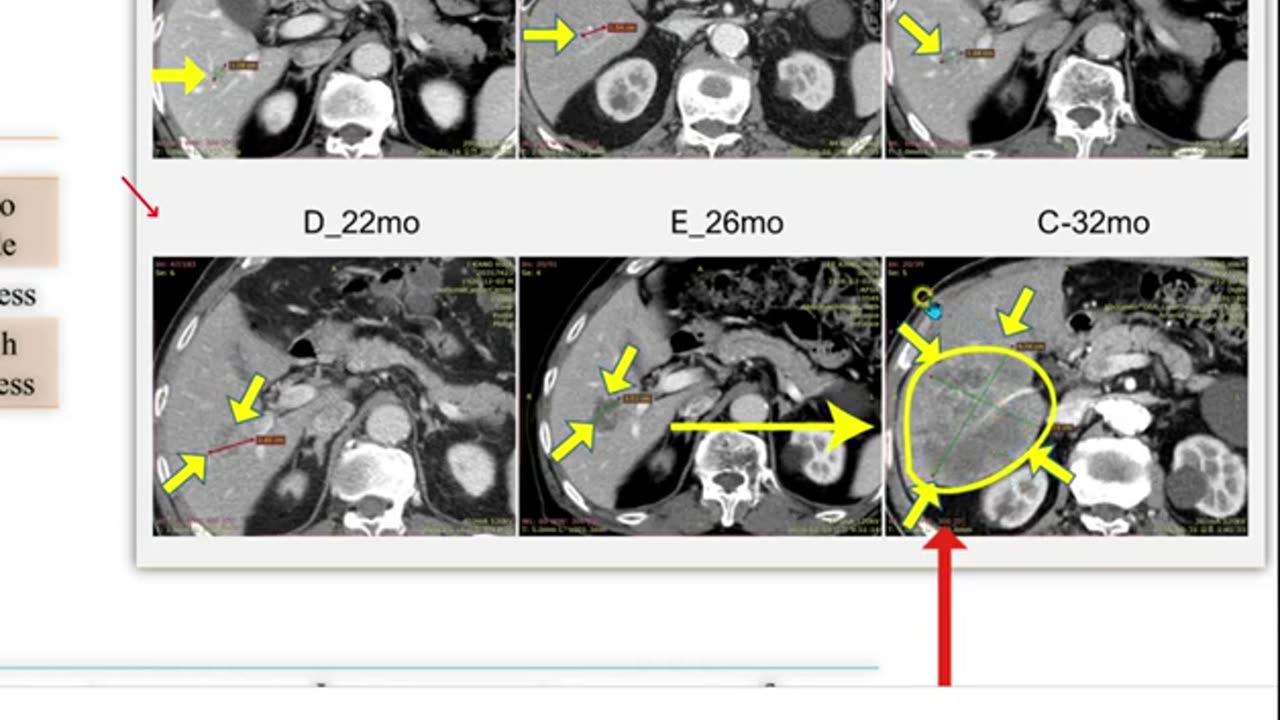

대장암 간폐전이 완치 태음인 1-2, 반룡인수한의원, 강남구청역, 한태영원장님, 사상의학